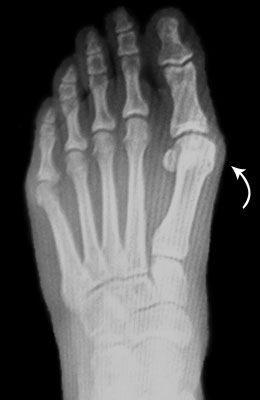

Before

After

Osteotomy Bunionectomy after

Osteotomy Bunionectomy

In this procedure (also known as an “Austin Bunionectomy), a cut in the bone was made, and the bone was shifted to realign the joint. A screw was placed to hold this new alignment in place. Notice the improved alignment of the great toe joint.